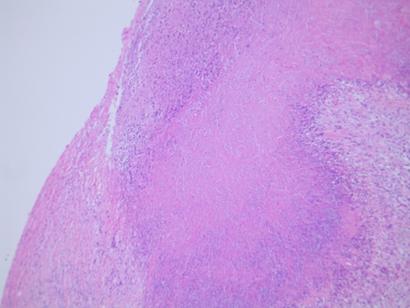

- histology:

- central zone of fibrinoid necrosis surrounded by palisading histiocytes

Rhematoid lung nodule